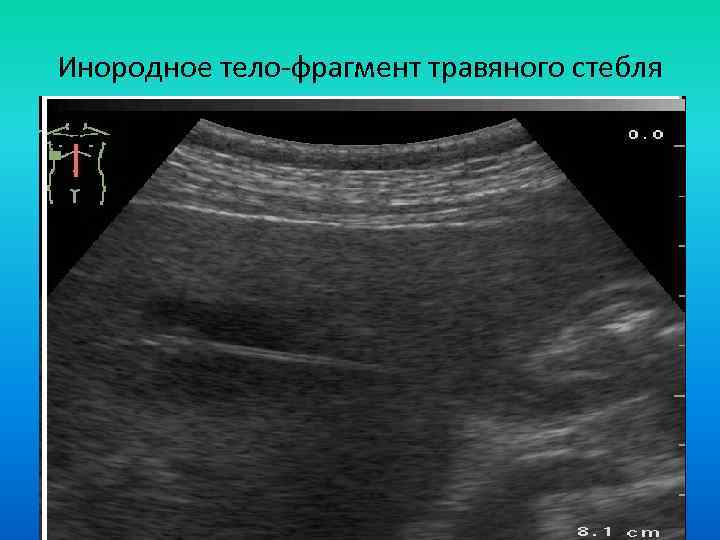

Инородное тело-фрагмент травяного стебля Инородное тело-фрагмент травяного стебля